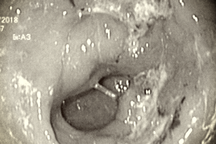

Bác sĩ sẽ sử dụng ống nội soi để đưa vào thực quản xuống đến dạ dày để quan sát bên trong. Ưu điểm của nội soi cho phép quan sát được các thay đổi của niêm mạc dạ dày và tiến hành sinh thiết qua nội soi để có chẩn đoán mô bệnh học, qua đó cho phép chẩn đoán các ung thư dạ dày tại chỗ hoặc xâm lấn.

Ngoài ra các tổn thương tiền ung thư cũng có thể thấy được trên nội soi như: viêm teo, loét, polyp hoặc các tổn thương dạng tăng sản biểu mô tuyến. Sinh thiết các tổn thương nghi ngờ cũng có thể phát hiện các tổn thương tiền ung thư trên mô bệnh học như viêm teo, tăng sản, dị sản, loạn sản…

Nội soi cũng có thể đánh giá tình trạng có hay không có nhiễm Helocobacter Pylori, một trong số những yếu tố nguy cơ gây ung thư dạ dày, giúp cho việc điều trị dự phòng.

Ung thư dạ dày là loại bệnh lý tiến triển khá nhanh, do đó trong sàng lọc, vai trò của nội soi dạ dày chủ yếu tập trung vào phát hiện sớm các tổn thương tiền ung thư.